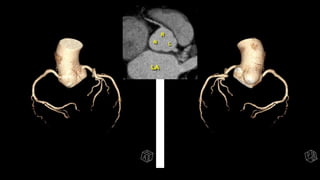

Anatomía cardiaca normal. Tomografía.

1. Nivel de los 5 vasos

2. Nivel del arco aórtico

3. Nivel de la ventana aórtico pulmonar

4. Nivel de la arteria pulmonar

5. Nivel cardiaco alto

6. Nivel cardiaco bajo